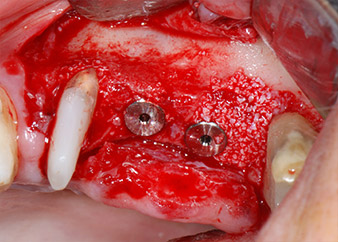

The implants (Restore, Keystone Dental, diameter 3,75 mm, length 8.0 mm) were placed with the implant motor

(Figs. 11 and 12).

ready for the cover screws

Fig. 12: Both implants in place and ready for the cover screws.

Bone deficiencies around the implants, at the mesial aspect of tooth 27 and around the buccal root of tooth 24, were filled with xenogeneic bone substitute particles and covered with an absorbable collagen membrane (Bio-Gide, Geistlich Biomaterials) for GBR augmentation (Figs. 13 and 14).